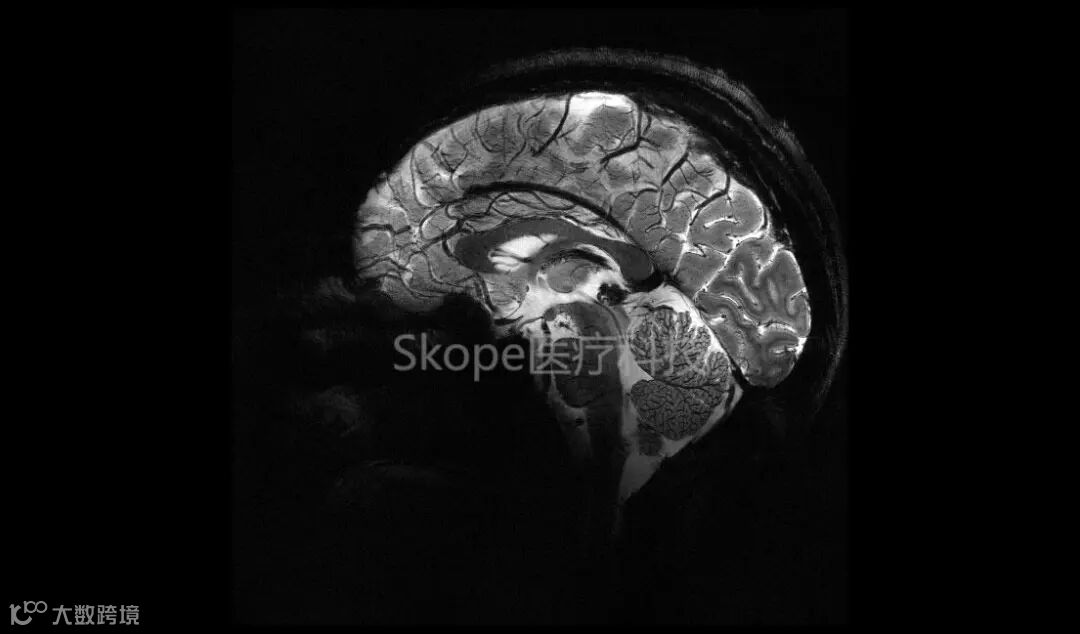

11.7T人体成像 © CEA

11.7T的首次扫描成像(南瓜与人脑标本) © AROMA